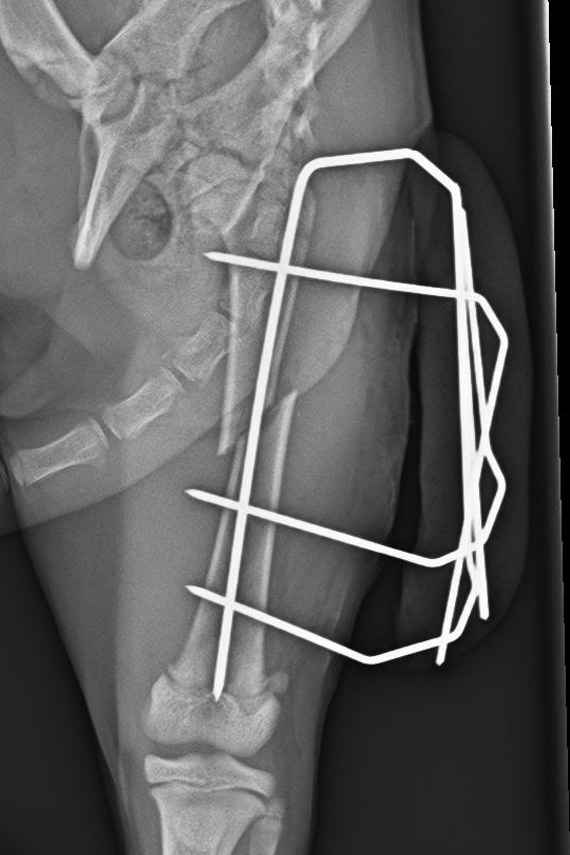

Versorgung einer Femurfraktur einer jungen Katze mit einem externen Fixateur.